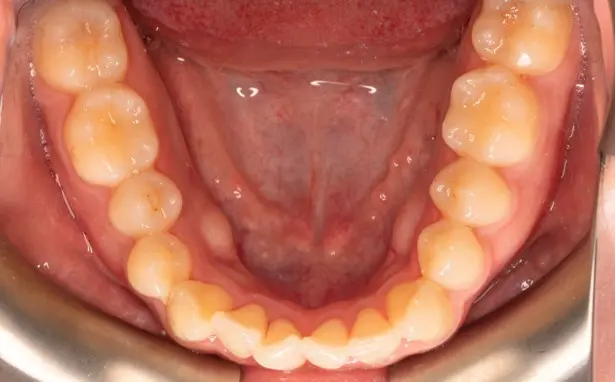

Crowding

Before

After